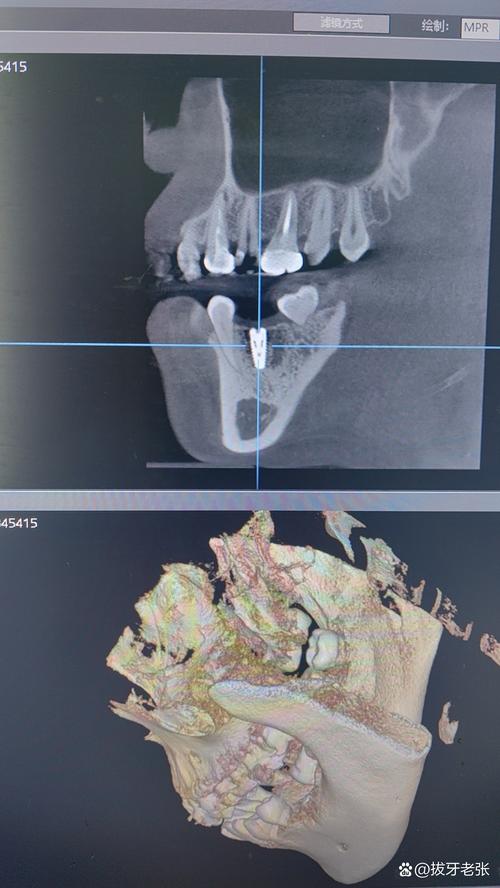

种牙CT检查首选锥形束CT(CBCT),而非传统螺旋CT,CBCT具有辐射剂量低(仅为螺旋CT的1/10-1/100)、空间分辨率高(可达0.1mm)、扫描时间短(10-30秒)等优势,且能三维重建牙槽骨、邻牙、神经血管等结构,为种植体植入位置、角度、深度提供精确数据,普通螺旋CT因辐射剂量高、层厚较厚(通常1-5mm),难以清晰显示牙槽骨的细微骨纹理和重要解剖标志,仅适用于复杂病例的补充检查(如颌骨肿瘤、严重骨缺损)。

- 图像后处理:医生需通过专业软件(如Dexis、OnDemand)进行三维重建,多平面观察(MPR、CPR)、测量骨量、模拟种植体植入路径,确保方案可行性。